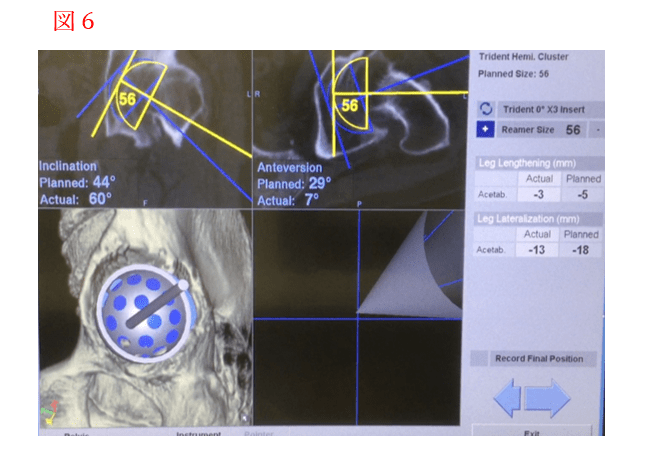

人工股関節全置換術の手術を行う際に最も大切なことは、手術前計画をしっかりと行い、それを実際の手術時に正確に再現させることが重要であります。具体的にはインプラントを適切な位置に適切な角度で強固に設置し、そして脚の長さをベストな長さに整えることが重要です。インプラントの設置位置・設置角度の不良は、手術後の脱臼や、インプラントの摩耗などの原因となります。手術前に撮影したCTの三次元構成画面を参照しながら骨盤座標系を作成し、これらを参照しながら術前計画通りにインプラントを最適な位置に設置し、安全・安心な手術を実現させるために、私たちの施設ではナビゲーションシステムを導入しております。

手術ナビゲーションシステムは、カーナビゲーションと同様に、手術中に骨の三次元的な位置を正確に把握し、術前計画(図1)に沿って手術操作を行うことを手助けします。カーナビゲーションはGPS用人工衛星からの電波を車が受信して、もともと描かれている地球の地図上に車の現在位置を示します。一方、手術ナビゲーションシステムでは、骨(骨盤)にはもともとは地図が描かれておりません。そこで、骨(骨盤)に赤外線マーカーを取り付け、ここから出される赤外線を三次元センサーのカメラで、術前に撮影したCTの三次元的構造を捉えることにより骨に地図を描くことが可能になります。図2が当院で使用している手術ナビゲーションシステム(Stryker 社製 CT-based Hip Navigation)の機械本体の概観で、本体に三次元センサーの 赤外線カメラが取り付けられています。図3がこのシステムの赤外線マーカー(トロッカー)で、電池 が内蔵されており複数のLEDから赤外線が発光されるようになっています。この赤外線マーカー(トロッカー)を骨や術具に取り付けます。 術中は、図3のように、骨(骨盤)にピンを2本刺して赤外線マーカー(トロッカー)を取り付けます。次に、図4①のようにLED付きポインターの先端で術前に撮影した骨盤骨CT画像上の重要な約5か所の取得(Paired point matching)と、図4②他の部位の骨盤骨表面(最低30ポイント)の取得で位置情報を集め(surface geometry matching)、 術前CT画像上の骨の画像とマッチングさせ、ここで始めて骨盤骨上に地図が描かれます。手術中は、この地図を利用し、常に骨の位置や向きを正確に計測することができ、モニター画面上で術前計画を表示させながらまた、術具にも赤外線マーカーを取り付け(図5)、術具の位置と向きを確認できて、確実に手術前に計画していたインプラントの設置を正確に行うことができます(図6)。これがナビゲーションシステムの最大のメリットであります。